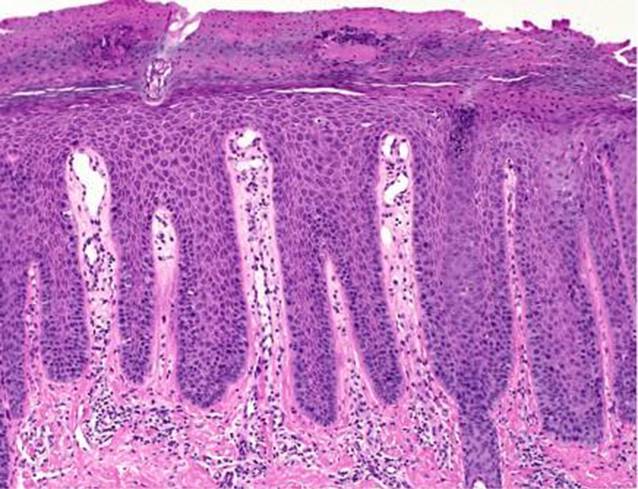

Zur weiterführenden Diagnostik wurde eine Probebiopsie (4-mm-Stanze) in Lokalanästhesie entnommen (Abb. 2).

Abb. 2

Der histopathologische Befund ergab eine psoriasiforme Epidermishyperplasie mit Parakeratose und Verlust des Stratum granulosum. Auffallend sind auch verlängerte dermale Papillae mit teleangiektatisch erweiterten Kapillaren